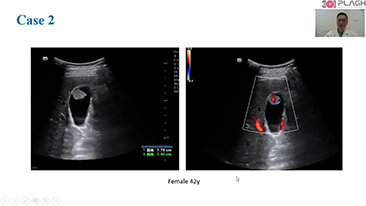

General Imaging

Mindray Resona General Imaging solutions help clinicians realize more accurate and efficient diagnosis and treatment results through comprehensive subdivision application probes and efficient clinical application tools.

General Imaging Products